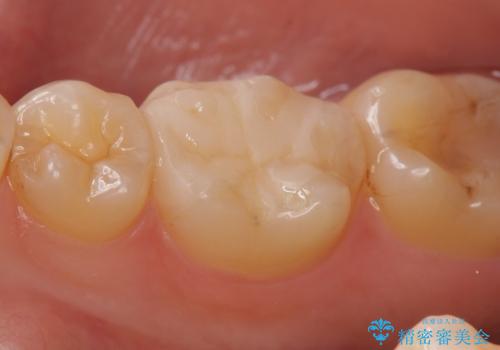

- 右下の銀歯が気になるといらっしゃった方の症例です。

右下6番目の銀歯を除去後、セラミックインレーによる修復を行いました。

当院のセラミックインレーはemaxという強度と審美性に優れた材料を使用しています。

またプレス方式でインレーを製作しているため、削り出しで製作するCADCAMより優れた適合性も持ち合わせており、虫歯が再発しにくい修復物です。